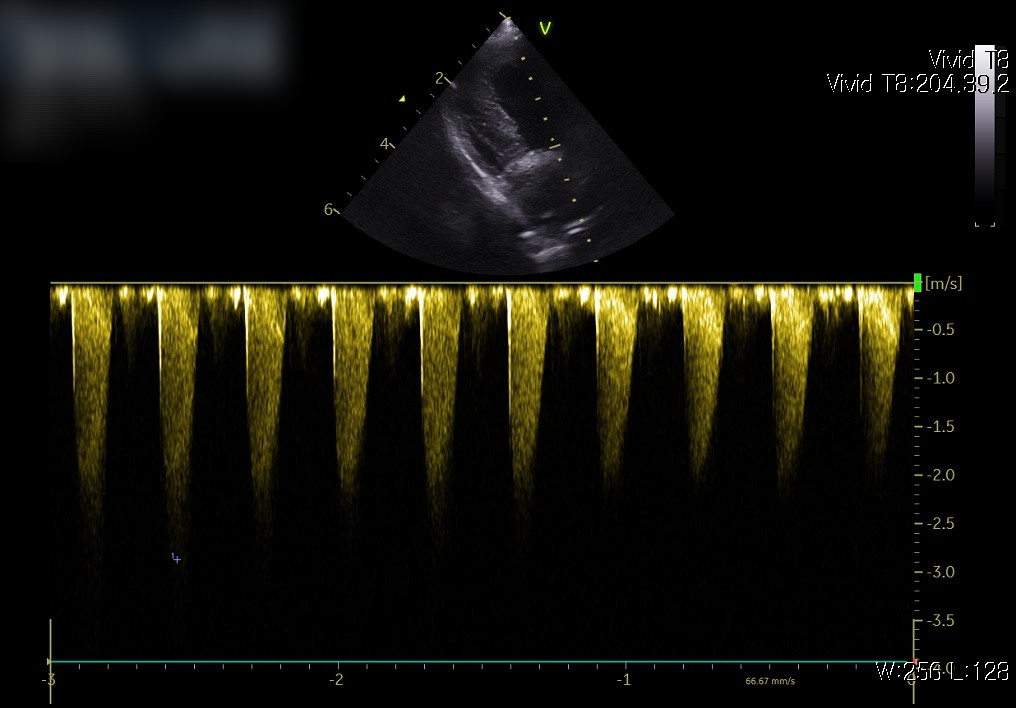

📌 심장 초음파

초음파 검사는 심장의 구조와 기능을 직접 확인할 수 있는 가장 중요한 검사입니다. 판막이 제대로 닫히는지, 심실 벽의 두께는 정상적인지, 혈액이 원활하게 흐르는지를 정밀하게 평가할 수 있습니다.

심장 초음파 사진: 판막 기능 이상과 혈류의 역류 소견 확인